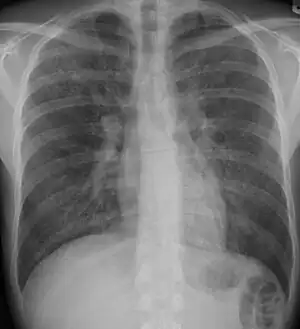

-

Chest radiograph showing interstitial lung disease -